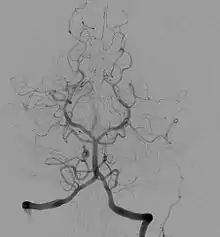

Angiografia cerebral

A angiografia (arteriografia) cerebral é uma técnica utilizada para a detecção de anomalias dos vasos sanguíneos cerebrais - como sejam uma dilatação arterial (aneurisma), uma inflamação (arterite), uma configuração anormal (malformação arteriovenosa) ou uma obstrução vascular (acidente vascular cerebral). Foi inventada pelo médico português António Egas Moniz, que a realizou pela primeira vez com sucesso num doente vivo em 1927.

É injectado contraste radiopaco (substância visível com o Raio X) numa artéria que irriga o cérebro, revelando assim o padrão do fluxo sanguíneo cerebral nas radiografias. A Ressonância Magnética também pode ser utilizada para mostrar o padrão do fluxo sanguíneo das artérias do pescoço e da base do cérebro, mas as imagens apresentam uma qualidade inferior às da angiografia cerebral.